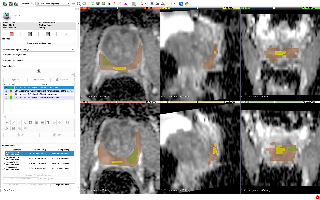

磁共振图像脊柱结构多类别三维自动分割

| 名称 | 标注内容 | 类型 | 模态 | 数量 | 标签格式 | 文件格式 | License |

|---|---|---|---|---|---|---|---|

| 磁共振图像脊柱结构多类别三维自动分割 | 椎骨和椎间盘 | 分割 | MRI T2WI | 172 | 0/1 | nii | Custom |